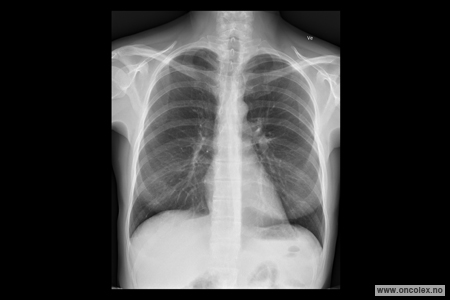

Røntgen toraks er en røntgenundersøkelse som tas for å se på lunger, hjerte og lymfeknuter i brystskilleveggen mellom lungene.

Du blir bedt om å kle av deg på overkroppen og stå foran et røntgenapparat. Deretter vil du få beskjed om å trekke pusten dypt inn og holde pusten når bildene blir tatt. Det tas front- og sidebilde. I spesielle tilfeller, for eksempel dersom du ikke klarer å stå oppreist, kan bildene tas mens du sitter eller ligger i sengen.